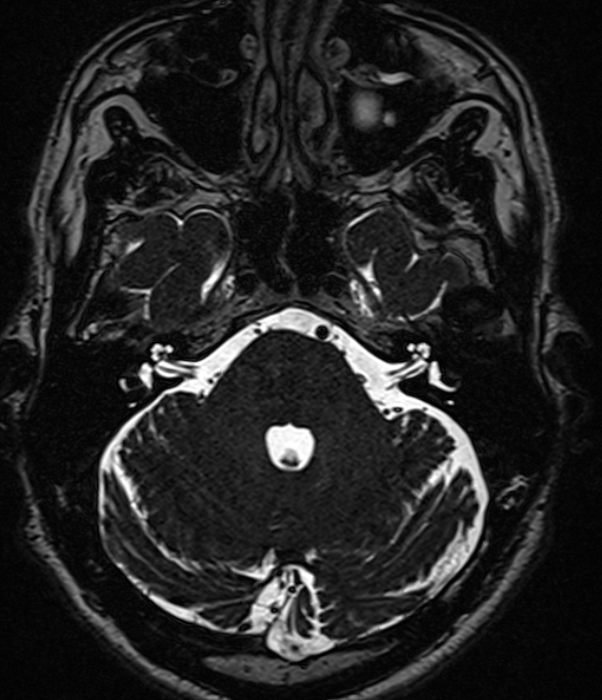

МРТ головного мозга при вазоневральном конфликте (тройничный нерв, вестибулокохлеарный нерв, мостомозжечковый угол) – важный метод исследования, который позволяет оценить структуры мосто-мозжечковых углов, взаимоотношения артерий и черепно-мозговых нервов.

Показания для проведения МРТ головного мозга при вазоневральном конфликте:

• шум в ушах;

• снижение слуха;

• головокружение;

• невралгия тройничного нерва;

• гемифациальный спазм.